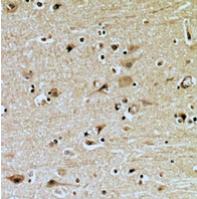

Immunohistochemical analysis of ZNRF2 staining in human brain formalin fixed paraffin embedded tissue section. The section was pre-treated using heat mediated antigen retrieval with sodium citrate buffer (pH 6.0). The section was then incubated with the antibody at room temperature and detected using an HRP conjugated compact polymer system. DAB was used as the chromogen. The section was then counterstained with haematoxylin and mounted with DPX.